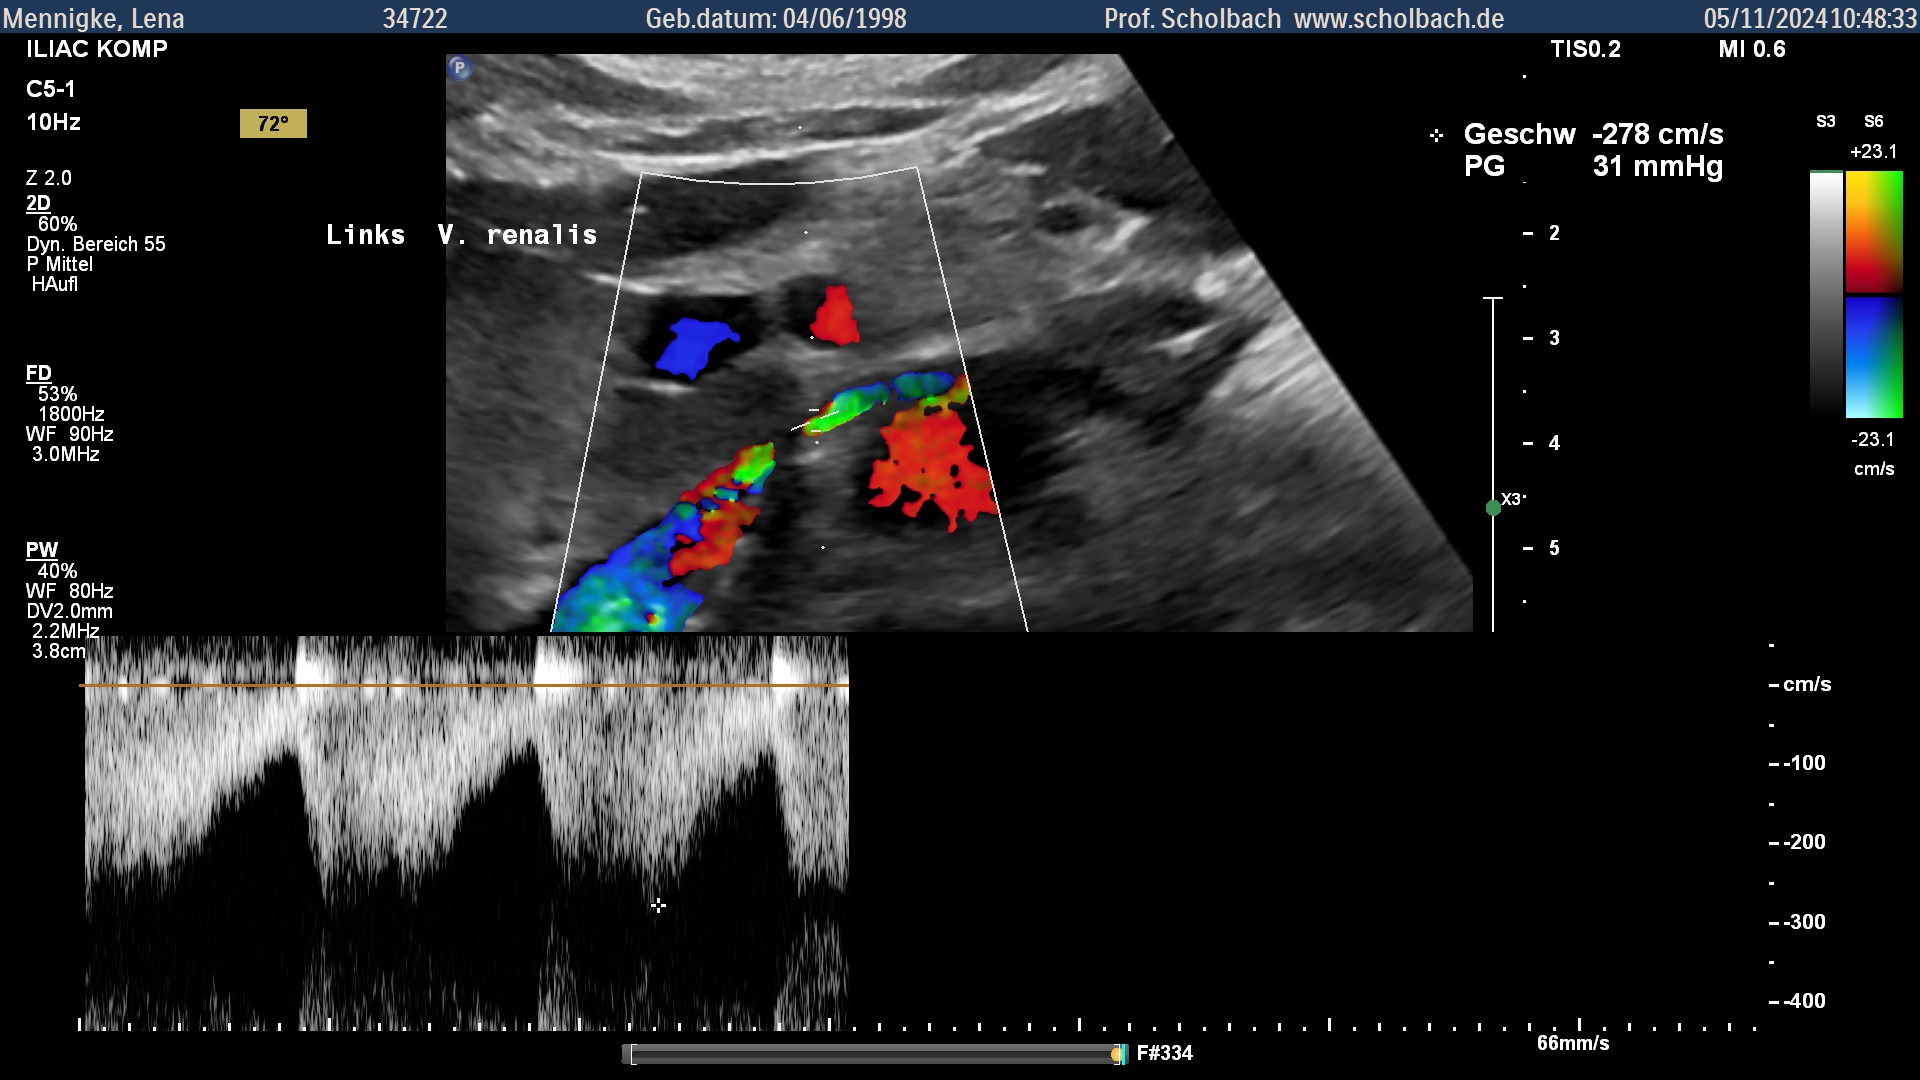

Her left renal vein is also severely compressed (Nutcracker Syndrome), which means that the kidneys can no longer be properly supplied with blood. In addition, as a result of the compression, another blood vessel has formed through which blood flows to the spine (tronc-reno-rachidien). This can have serious neurological consequences such as paralysis and TIAs (so-called mini-strokes). Furthermore, long-term reduced blood flow to the organs and malnutrition can lead to serious consequences.

Auch die linke Nierenvene ist stark komprimiert (Nussknackersyndrom), wodurch die Nieren nicht mehr richtig durchblutet werden können. Dadurch hat sich bereits ein neues Blutgefäß gebildet, durch welches Blut zur Wirbelsäule fließt (tronc-reno-rachidién). Dies kann schwere neurologische Folgen haben wie Lähmungen und TIAs (sog. Mini-Schlaganfälle). Weiterhin kann es zu schwerwiegenden Folgen durch langjährige Minderdurchblutung der Organe und Mangelernährung kommen.